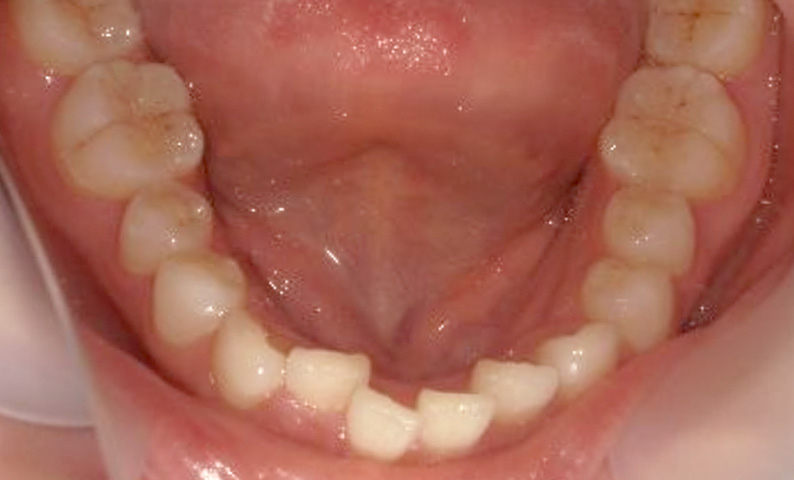

症例_001 下顎だけの部分矯正

治療期間:6ヶ月金額:27万円+税女性前歯のガタガタ下の前歯だけ

| Before | After |

|---|---|

|